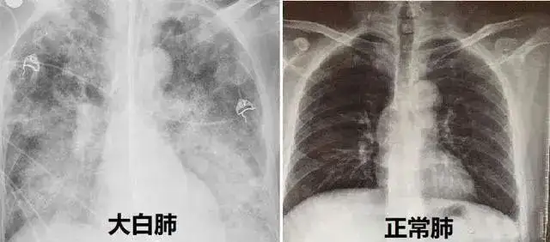

东南大学附属中大医院呼吸与危重症医学科主任章锐锋介绍,白肺不是一种具体的疾病,而是疾病的一种影像学表现。我们的肺是由肺泡组成的,正常情况下肺泡里充满了空气,进行CT或X线检查时,射线穿过肺泡,影像的表现应该是黑色的区域。

但当肺泡里边出现炎症和感染,有渗出液和炎性细胞时,肺泡就被这些渗出液或炎性细胞填充,肺脏中的气体含量减少,这样射线就穿不透,在影像学上的表现就是出现了白色区域,这个白色区域反映出来的是渗出物的影像学表现,并不是说肺脏的组织和实体变成了白色。

并不是只要肺部出现了炎症都叫白肺,比较严重的肺炎表现才会出现白肺。一般来讲,肺部的炎症比较重、渗出液较多时,即白色的影像区面积达到70%~80%时,才在临床上把它称为白肺。